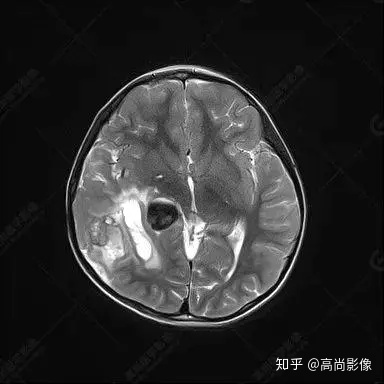

右側(cè)顳葉腫瘤切除術(shù)后(具體不詳):右側(cè)顳部骨質(zhì)不連續(xù)呈術(shù)后改變,右側(cè)顳葉術(shù)區(qū)見片狀長(zhǎng)T1長(zhǎng)T2信號(hào)影,F(xiàn)LAIR呈低信號(hào);術(shù)區(qū)后方右側(cè)顳枕葉見一巨大占位性病變影,邊界欠清,大小約6.2×5.8×4.3cm(前后×左右×上下),信號(hào)不均勻,T1WI呈等稍低信號(hào)間雜少許高信號(hào),T2WI呈高稍低混雜信號(hào),DWI示部分病灶彌散受限,相應(yīng)ADC圖減低,磁敏感序列見部分呈極低信號(hào),增強(qiáng)掃描可見明顯不均勻強(qiáng)化,鄰近硬腦膜及小腦幕增厚并明顯強(qiáng)化;另延髓右前方及右側(cè)橋小腦角區(qū)見一不規(guī)則形異常信號(hào)影,大小約3.2×1.3×3.7cm(左右×前后×上下),呈長(zhǎng)T1稍長(zhǎng)T2信號(hào),F(xiàn)LAIR呈等信號(hào),DWI未見受限,增強(qiáng)后明顯均勻強(qiáng)化,鄰近腦膜明顯強(qiáng)化。鄰近腦實(shí)質(zhì)及右側(cè)顳角明顯受壓;左側(cè)大腦半球未見局灶性信號(hào)異常,中線結(jié)構(gòu)稍左移。

右側(cè)顳葉腫瘤切除術(shù)后:現(xiàn)術(shù)區(qū)后方右側(cè)顳枕葉及延髓右前方占位,右側(cè)顳枕部硬腦膜及小腦幕明顯強(qiáng)化,結(jié)合既往影像資料,考慮為胚胎源性惡性腫瘤,如非典型畸胎樣/橫紋肌樣瘤(AT/RT)或原始神經(jīng)外胚層腫瘤(PNET)。